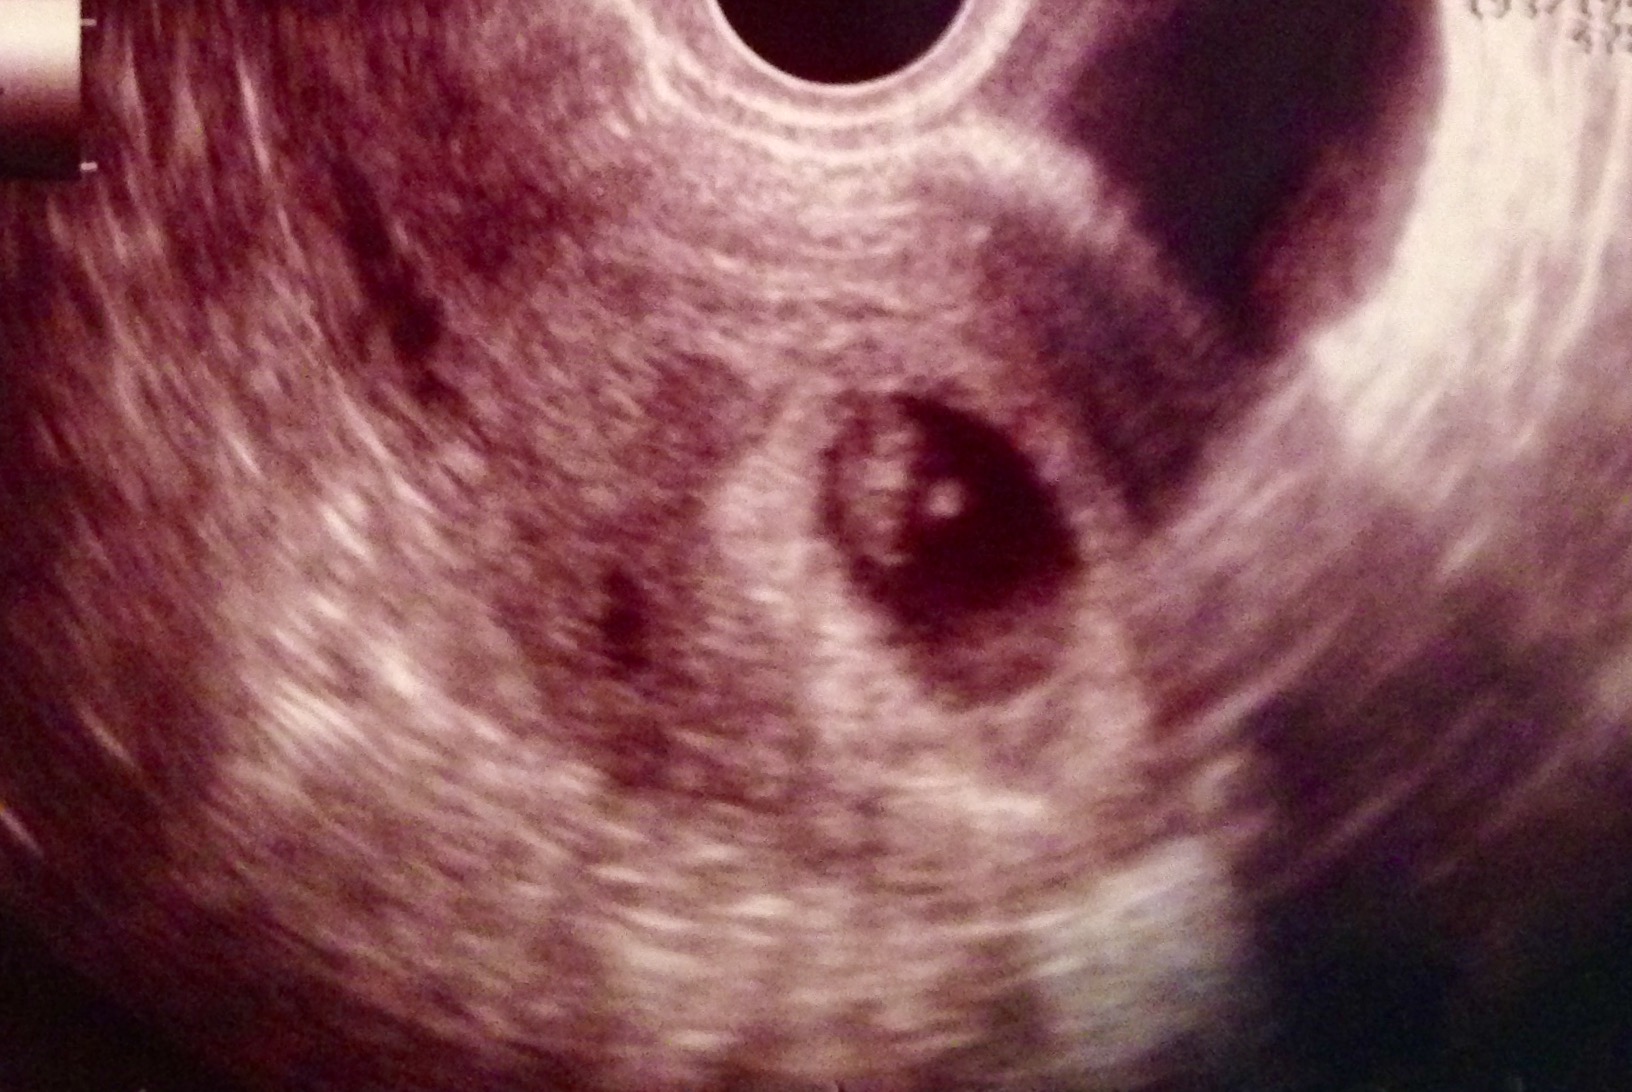

ultrasound1 Published February 12, 2017 at 1632 × 1092 in The Story I Never Wanted to Tell Next » Share this:TweetMore Email a link to a friend (Opens in new window) Email Print (Opens in new window) Print Like Loading...